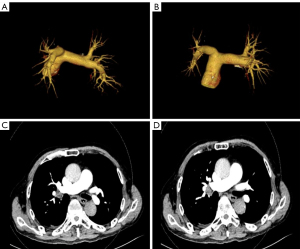

On Day 3, imaging confirmed pulmonary embolism via pulmonary vascular CTA, and ultrasound of both lower extremities revealed multiple arterial plaques and thrombosis in the intermuscular veins of the right lower leg (Figures 3,4). Anticoagulation therapy was intensified with nadroparin (4,100 IU Q12H). On Day 4, the patient developed respiratory failure [peripheral oxygen saturation (SpO2) <90%], his D-dimer levels exceeded 50,000 µg/L, and his platelet count dropped to 37×109/L, presenting a “thrombosis-bleeding” treatment dilemma. Thrombocytopenia was initially attributed to eosinophil-mediated consumptive coagulopathy, with serial platelet counts showing a decline from 64×109/L (admission) to 37×109/L (Day 4). Heparin-induced thrombocytopenia (HIT) was ruled out due to: (I) the onset of thrombocytopenia within 48 hours of nadroparin initiation, which was shorter than the typical 5–10-day latency period for HIT (19); and (II) a platelet count decline of <50% from the baseline, which was below the diagnostic threshold for HIT (20).

This case exemplifies the HES-associated “thrombotic storm;” within 24 hours of admission, the patient exhibited rapidly progressive neurological deficits, an exponential rise in D-dimer, and multi-system embolism (cerebral, pulmonary, and lower limb venous thrombosis), confirmed by multimodal imaging, reflecting eosinophil-mediated fulminant thrombosis. A distinct “three-level thrombus cascade” was observed: (I) eosinophil granule proteins disrupted vascular endothelial tight junctions and activated the extrinsic coagulation pathway; (II) eosinophil-derived microparticles carrying tissue factor bound to platelet glycoprotein VI, creating a procoagulant microenvironment; and (III) eosinophils released plasminogen activator inhibitor-1 at concentrations ~15 times higher than normal, stabilizing thrombi and impairing fibrinolysis (32). A “biphasic dissociation” between cerebrovascular imaging (CTA/CTP) and pathology was notable: (I) eosinophil infiltration caused blood-brain barrier disruption and microvascular spasm rather than mechanical large-vessel occlusion; and (II) positron emission tomography–CT demonstrated CD125+ eosinophil aggregation in the infarction area, indicating localized inflammation-thrombosis crosstalk (33). The mesenteric embolism likely originated from eosinophil-endothelial adhesion and coagulation-complement interactions (34).